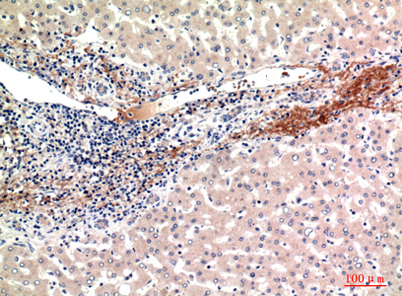

| Dilutions: | Western Blot: 1/500 - 1/2000. IHC-p: 1:100-1:300. ELISA: 1/20000. Not yet tested in other applications. |